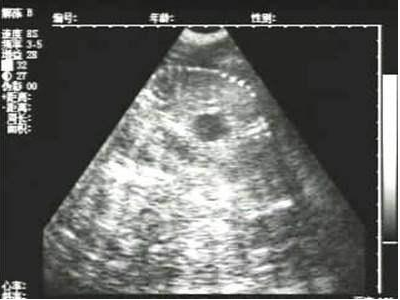

需要注意的是,出現云團狀必須雙側檢查加以確認.根據B超機顯示圖我們大致可以判斷孕齡.圖像呈橢圓或者卵圓形大致為30天左右孕齡;圖像呈橢圓形或者卵圓形外,有明顯發亮骨骼圖像大致為50孕齡左右;圖像囊胚消失,發亮處隱約可見竹節狀東西為成型胎兒骨骼,一般為后期80孕齡以后。一般B超機成像會出現三種顏色,白色、黑色、灰色。白色為密度較高的物體,如骨骼或者結實.黑色一般為液體,包括血液、羊水、組織間隙液體、炎癥病灶等?;疑话銥閷嵸|性物質,如肌肉。

懷孕后期胎兒骨骼圖像